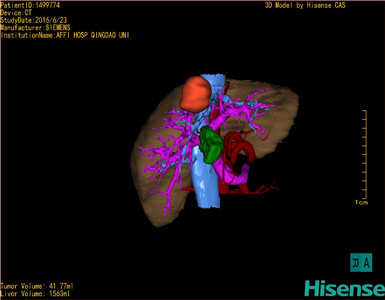

将0.625mm双源薄层CT资料的静脉期和动脉期Dicom格式文件导入海信CAS系统。

通过调节窗宽窗位调整CT序号,对肿瘤,肝实质,胆囊,下腔静脉,肿瘤,肝动脉、门静脉及肝静脉等进行三维重建;系统自动计算肿瘤体积和肝脏体积。

模拟手术操作,自动计算切除肿瘤体积。肝脏体积为1536ml,肿瘤体积为41.77ml,肿瘤体积为肝脏体积2.7%,通过比60-70岁正常肝脏体积为1262.7±284.31ml,通过术前模拟手术,精准判断切除后剩余肝脏体积能耐受,避免肝衰竭发生。

术前手术方案的规划。

探查见:肝脏呈小结节性肝硬化,肝脏体积缩小,肝左外叶较小。肝周围少量腹水。右肝前叶Ⅷ段交界处,可触及直径5cm不规则肿块,侵及肝被膜,呈灰白色。考虑肝脏较小,硬化明显,决定行肝部分切除术。断肝圆韧带,镰状韧带至第二肝门,断肝右三角韧带,冠状韧带,肝结肠韧带,游离右半肝。沿肿瘤边缘约1cm,依次钳夹、切断、结扎肝断面各结构,切除肿瘤及部分肝组织。肿瘤侵犯肝中静脉,切除后肝中静脉5-0prolene线仔细缝合。肝断面渗血处分别缝扎止血,填塞止血敷料后,将创面对拢缝合。温蒸馏水1000ml冲洗腹腔,止血,于肝断面旁放置引流管1根于右侧腹穿孔引出。清点纱布器械无误,分层缝合腹壁切口。术后血压120/68mmHg,术中出血约300ml,输RBC3u ,输血浆400ml。术后返PACU。

手术顺利,麻醉满意,解剖标本,部分肝呈纤维化,内有灰白色质韧结节,送病理检查。病理检查结果:肝(VIII段)低分化癌伴大片坏死。手术时手术者可开启Hisense CAS系统手势控制功能,对肿瘤的解剖结构进行实时、全方观察、评估,起到术中导航作用。

术前三维重建:

重建图片